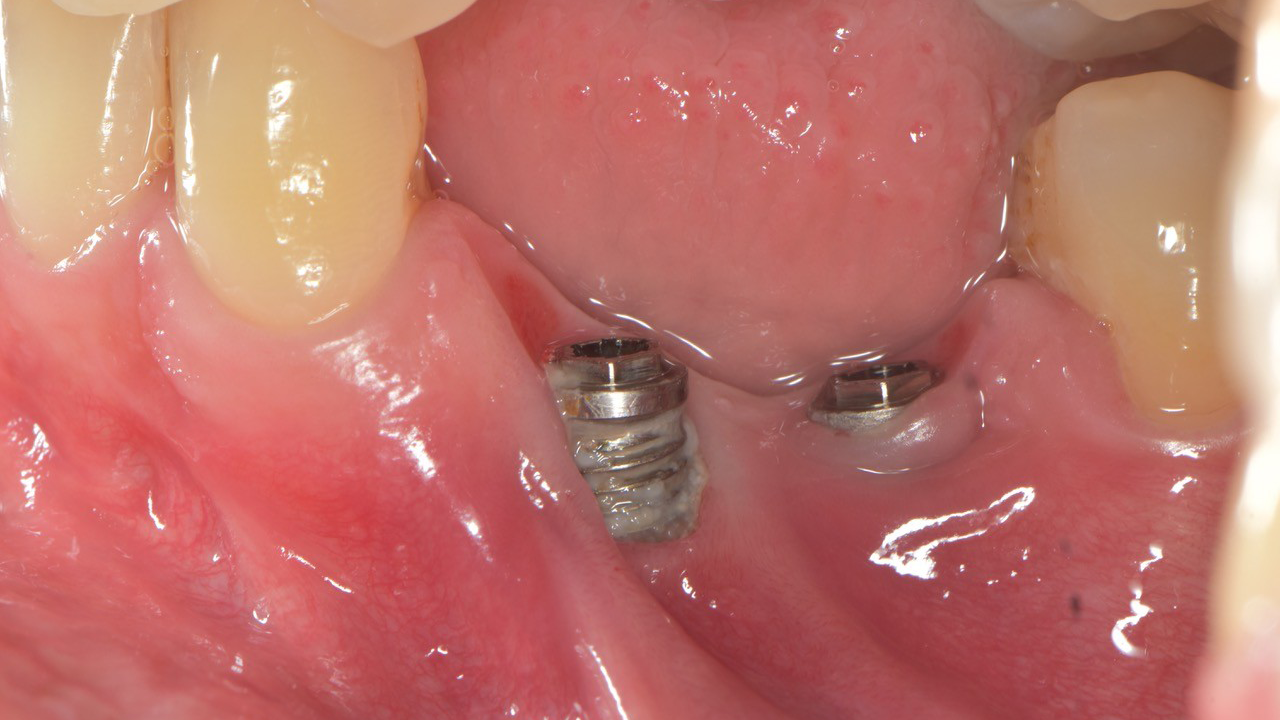

Periimplantitis stellt eine der bedeutendsten biologischen Komplikationen implantatgetragener Versorgungen dar und gefährdet langfristig die Stabilität und Prognose dentaler Implantate. Diese Falldiskussion beleuchtet Pathogenese, Risikofaktoren sowie diagnostische Kriterien und zeigt anhand klinischer Beispiele, wie ein strukturiertes therapeutisches Vorgehen entwickelt werden kann. Dabei werden sowohl nicht-chirurgische als auch chirurgische Behandlungsansätze bewertet und deren Wirksamkeit im individuellen Fall reflektiert. Die Analyse unterstreicht die Bedeutung frühzeitiger Intervention und konsequenter Nachsorge, um den fortschreitenden Knochenabbau zu kontrollieren und eine nachhaltige Implantatgesundheit zu sichern.